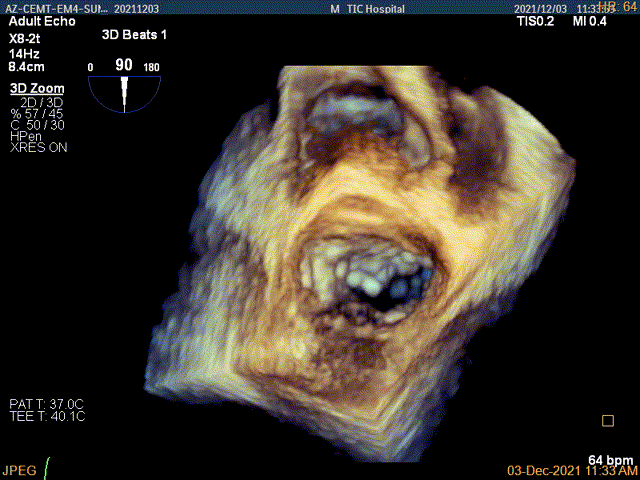

4Ch验证前后叶抓捕后有典型的bouncing征

x-plane平面测量确认后叶抓捕长度大于6mm

3D证实夹子AC区残余脱垂被禁锢住

3D-color证实无明确残余分流